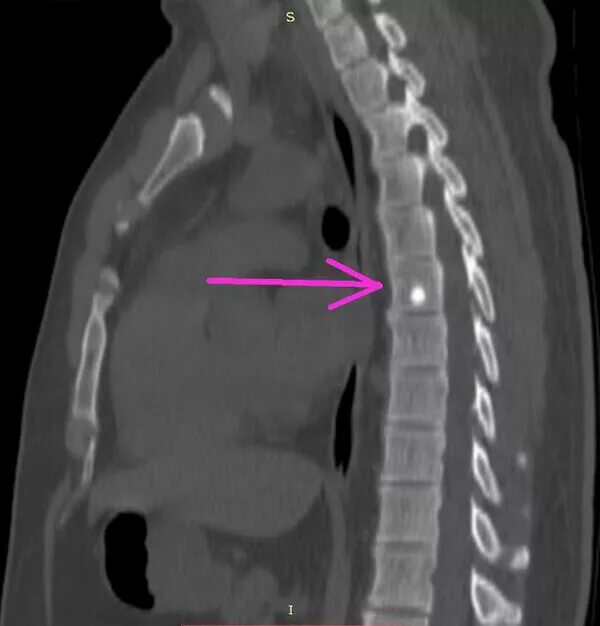

Остеосклероз грудного отдела